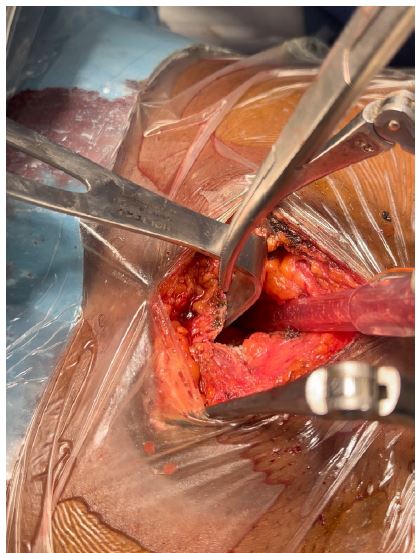

Patient was placed under general anesthesia, intubated and placed in the supine position on the surgical bed. Routing disinfection and surgical prepping was done. A subxiphoid median incision starting from xiphoid process to about 7 cm inferiorly was made. Subcutaneous and muscle fascia dissected and the xiphoid process amputated for better exposure of the pericardium. The bulging pericardium seen with a pericardiotomy made gently on the pericardium. Approximately 2 Liters of serohematic pericardial fluid was drained and a pericardial drain was placed in the pericardial space and connected to a self-expanding vacuum drain which was intended to drain the rest of the pericardial fluid. A biopsy of the pericardium was collected alongside 10cc of pericardial fluid and send for histo-cytology studies to determine the etiology of the effusion. Two thoracic drains were also placed and suture wounds closed up according to standard fashion and patient was taken to the surgical ward afterwards. Post operatively, cardiologist and infectious disease consults were requested for the patient. Post operative follow up was done. Histo-cytology results confirming TB as the etiology of the effusion. Patient was placed on anti TB medimedications by the infectious disease doctor and patient improved clinically and symptomatically with drained not producing anymore. Patient was later discharged 10 days post operatively and reviewed 2 weeks after with follow up cardiac echo and chest Xray not showing any pericardial effusion and pleural effusion respectively.